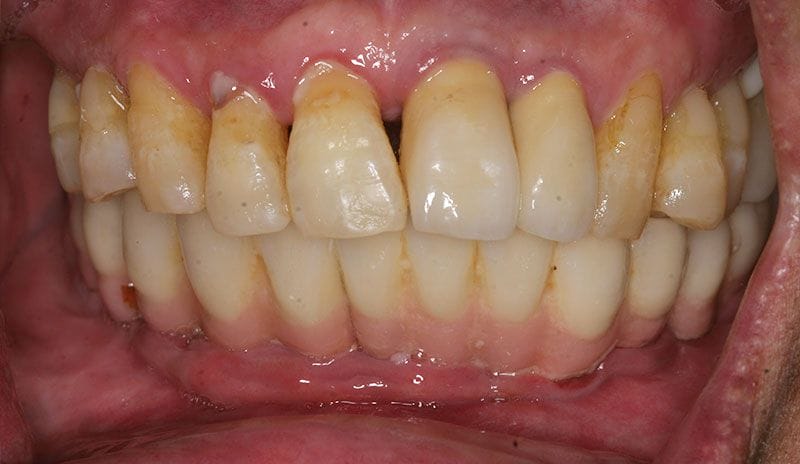

牙周病的症狀

通常牙周感染(牙周病)就像其他慢性感染一樣,是不會有明顯的疼痛症狀的,通常要等到較嚴重時,才會有明顯的不適,這就是牙周病的可怕之處。

牙周病症狀通常有以下幾點:

- 牙肉悶痛感

- 牙齦容易出血

- 牙齦紅腫

- 牙肉萎縮

- 牙齒對食物的敏感度提高(容易痠軟)

- 牙齒間隙越來越大

- 口臭

- 咬合位置改變,吃東西感覺不舒服

- 牙齒鬆動